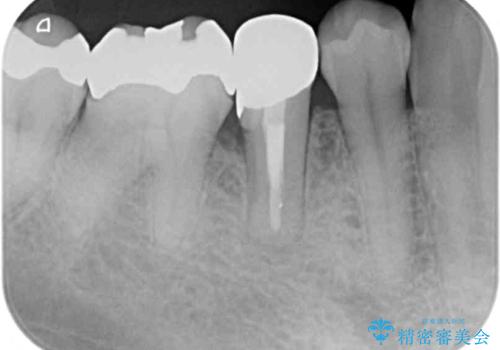

当初は根管治療を再度行うことで痛みが引くことを期待しましたが、該当歯の歯周ポケットが局所的に深くなっていることから、歯に穴が開けられているか破折している可能性が疑われました。

歯肉を開いたところ、周辺の歯槽骨は全て炎症で失われ、破折と同等の穴が開けられていることが分かったため、抜歯を行いフルジルコニアブリッジにて補綴することとしました。